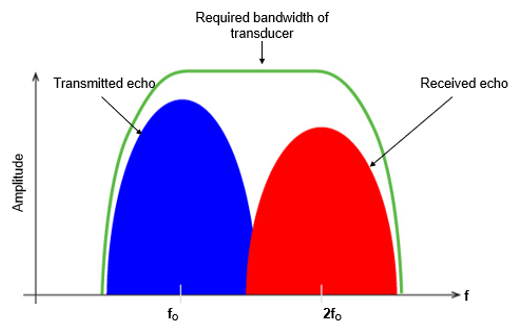

As we mentioned previously, the transmitted pulse consists of a range of frequencies centered around f0. In a linear medium, the echo pulse frequency is the same as the fundamental frequency but has lower energy, whereas the nonlinear medium results in harmonic waves of higher frequency and lower energy as shown in this figure. It is important to note that the majority of clinical US systems use second harmonic (ie, 2f0) echoes for THI image formation.

Now, let’s go deeper and explain the fundamental wave elimination techniques. The fundamental and the second harmonic frequencies are received together in the time domain as a combined distorted wave. High-quality THI primarily depends on the achievement of the complete elimination of the echoes at the fundamental frequency. Various techniques are used to remove the fundamental wave in THI, including bandwidth receive filtering, pulse inversion, side-by-side phase cancellation, and pulse-coded harmonics.

Bandwidth receive filtering is a signal processing technique in which lower frequencies that are more likely to have emerged from the fundamental beam are filtered out, and higher-frequency harmonic echoes are used to generate the image. In this technique, noise such as reverberation artifact and tissue aberrations diminishes and enhancement is improved.